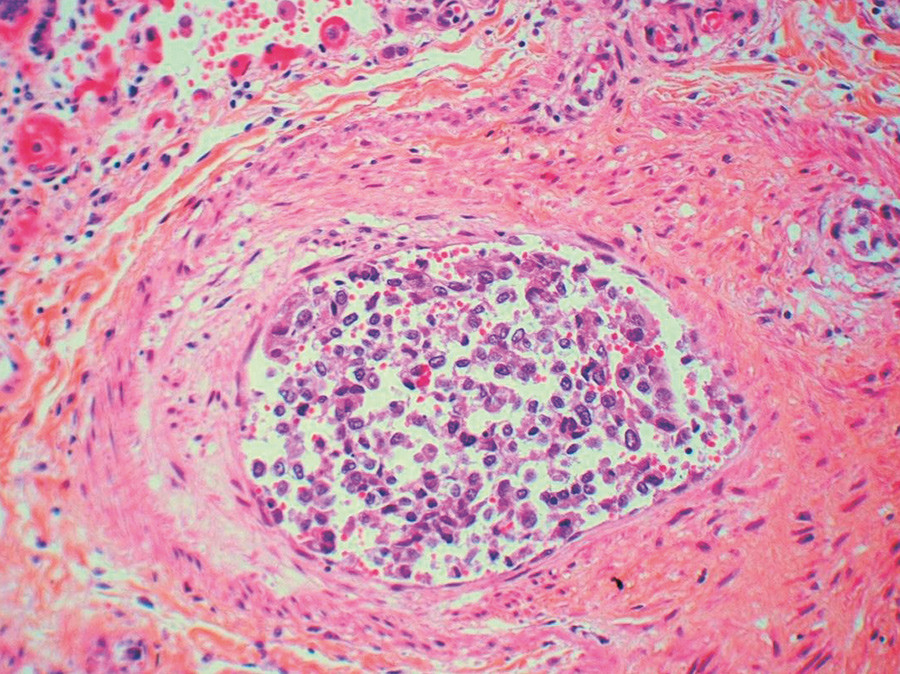

Mikroskopisk undersøkelse av vev fra metastasesuspekte lesjoner i lunge, lever, sternum og lymfeknuter bekreftet spredning fra adenokarsinom i mamma. I lungevevet var det flere ferske hemoragiske infarkter. I små arterier og arterioler var det multiple tumorembolier i varierende stadium av organisering (fig 3, fig 4). Veggen i små arterier og arterioler var betydelig fortykket med forsnevret lumen. Forandringene var dominert av eksentrisk intimafibrose (fig 5), men det var også hypertrofi av muscularis media.

De påviste karforandringene passer med at det forelå pulmonal hypertensjon, WHO-gruppe 5 (1), med tumorembolier i små lungekar som bakenforliggende årsak. Samlet kan dette passe med pulmonal tumor trombotisk mikroangiopati (pulmonary tumor thrombotic microangiopathy, PTTM).

Pulmonal tumor trombotisk mikroangiopati er vanskelig å diagnostisere og misoppfattes ofte som tromboembolisk sykdom. Andre benevnelser som brukes er karsinomatøs mikroangiopati, karsinomatøs arteriopati, karsinomatøs endarteritt og pulmonal tumoremboli. Denne tilstanden skiller seg fra vanlige tumorembolier ved at det også foreligger karforandringer som ved pulmonal hypertensjon.

De histopatologiske forandringene avviker lite fra forandringer ved pulmonal hypertensjon som følge av tromboembolisk sykdom. Karakteristisk ses eksentrisk, men også konsentrisk, fibrose av intima (2), mild eller fraværende hypertrofi av muscularis media (i motsetning til idiopatisk pulmonal arteriell hypertensjon) samt rekanalisering av tumortromber. Tilstanden ble først beskrevet av Brill & Robertson i 1937 som rask utvikling av høyresidig hjertesvikt grunnet tumoremboli (3). Den typiske pasienten har gjerne uttalt dyspné (3, 4), mens kliniske og bildediagnostiske funn kan være forholdsvis beskjedne.